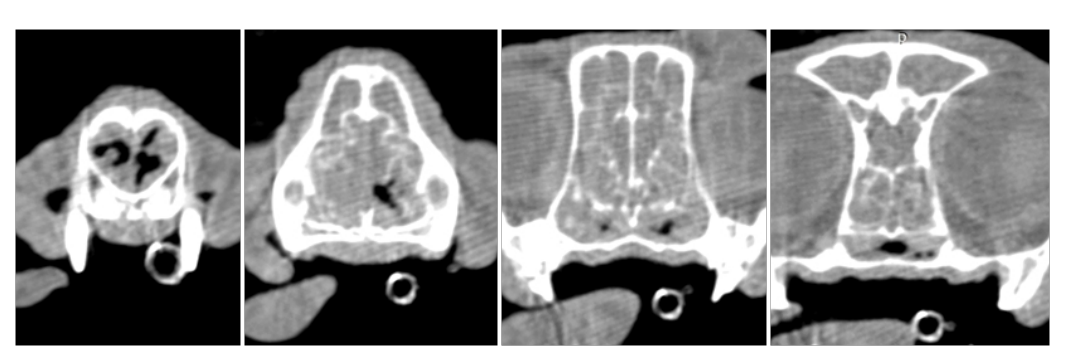

CT (Computed Tomography)

There are many indications for CT scan in animals - such as further evaluation of the nasal cavity, checking for ectopic ureters, finding abnormal vessels, etc.

Dog with normal nasal cavity and sinuses

Cat with a nasal mass - biopsy confirmed lymphoma

Another cat with nasal lymphoma

Cat with chronic rhinitis and sinusitis